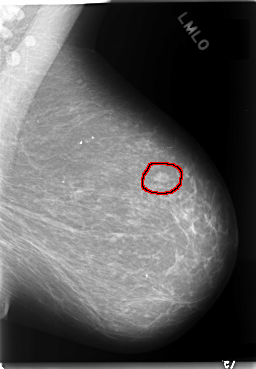

C_0084_1.LEFT_MLO

LEFT_MLO LINES 5896 PIXELS_PER_LINE 4088 BITS_PER_PIXEL 12 RESOLUTION 50 OVERLAY

FILE: C_0084_1.LEFT_MLO.OVERLAY

TOTAL_ABNORMALITIES 1

ABNORMALITY 1

LESION_TYPE MASS SHAPE LOBULATED MARGINS CIRCUMSCRIBED

ASSESSMENT 4

SUBTLETY 5

PATHOLOGY MALIGNANT

TOTAL_OUTLINES 1

BOUNDARY